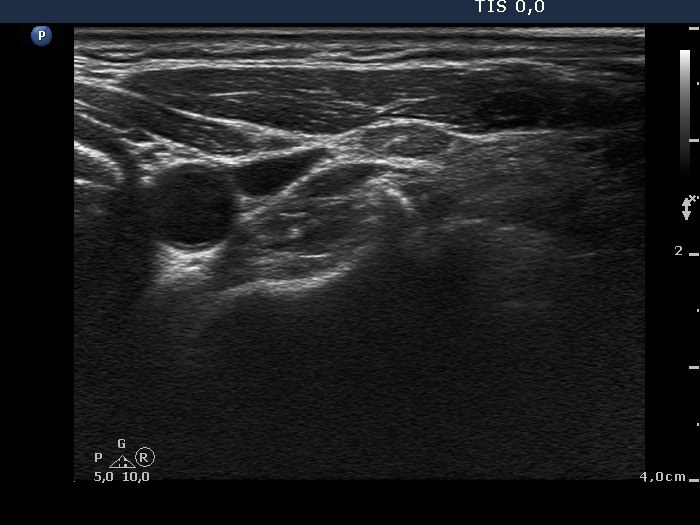

100 consecutive cases of papillary cancer - case 008 (ultrasonographic picture 5)

Lateral to the left lobe, transverse scan. A reactive-type lymph node is presented with regular hilum.